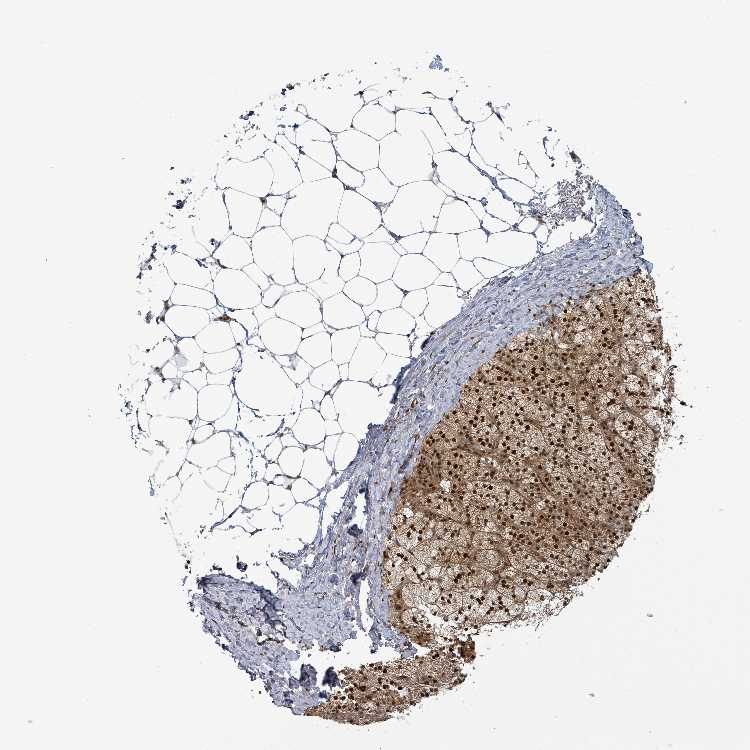

TISSUE PRIMARY DATA ADRENAL GLAND Show tissue menu

ADRENAL GLAND - Antibody stainingi

Antibody staining in the annotated cell types in the current human tissue is reported as not detected, low, medium, or high, based on conventional immunohistochemistry profiling in selected tissues. This score is based on the combination of the staining intensity and fraction of stained cells.

Each image is clickable and will lead to virtual microscopy that enables deeper exploration of all samples and also displays staining intensity scores, fraction scores and subcellular localization as well as patient and tissue information for each sample.

Antibody HPA036945Antibody HPA036946Antibody CAB009468

Glandular cells HighHighMedium